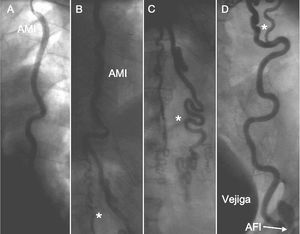

Varón de 62 años, ex fumador, con enfermedad pulmonar obstructiva crónica, diagnosticado de síndrome de Leriche en 1999, monorreno funcional y con stent en la arteria renal derecha desde el año 2000 a través de la arteria axilar izquierda. Ingresa por síndrome coronario agudo sin elevación del segmento ST, con cambios dinámicos en la cara lateral y elevación de troponinas (Tn) hasta 7,7 ng/dl. Se realizó coronariografía por arteria braquial izquierda 5F (arterias radial y cubital izquierdas filiformes y las derechas no palpables), y se encontró estenosis moderada en el tercio medio de la arteria descendente anterior (DA), oclusión crónica de la arteria coronaria derecha en el tercio medio y de la circunfleja (Cx) proximal (con retención de contraste), a partir de la DA había circulación colateral a los otros vasos, con buenos lechos distales. Además, tenía deterioro de la función ventricular (fracción de eyección del 40%) e insuficiencia mitral moderada. Se intentó angioplastia del vaso causal (Cx) que resultó fallida. Al final del procedimiento se realizó el sondaje de la AMI izquierda (fig. 1) que mostró circulación colateral abdominal hacia la arteria femoral izquierda. Debido al acceso vascular no realizamos inyección en la mamaria derecha. El paciente continuó con tratamiento médico, y experimentó lenta mejoría (desaparición de la angina de reposo y clínica de angina de esfuerzo CF II).

Fig. 1. Las imágenes A, B, C y D son secuenciales. A: sondaje de la arteria mamaria interna (AMI) izquierda desde arteria braquial izquierda. B y C: anastomosis a nivel abdominal de la arteria mamaria con la arteria hipogástrica a través de colaterales. D: drenaje de la arteria hipogástrica en la arteria femoral izquierda (AFI). *Se observa la circulación colateral.